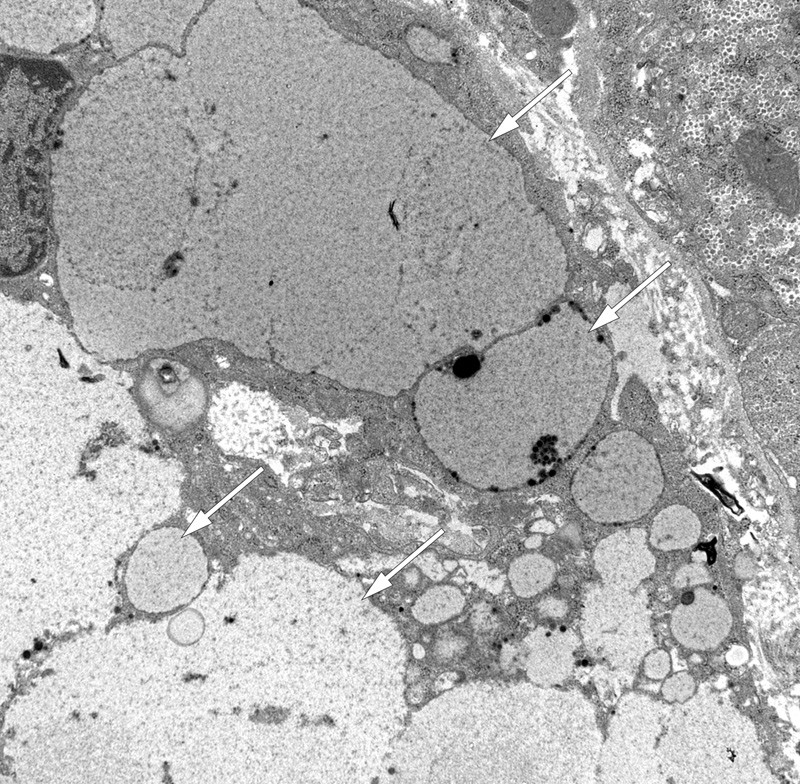

Transmission electron microscopy revealed groups of phagocytic cells with large intracellular vacuoles with uniform, finely granular contents of low electron density (Fig. 4). Within the hepatocytes, there were varying numbers of large lysosomes with finely granular contents of low electron density, along with small electron-dense grains and lipofuscin-like material. Non-specific secondary changes were also seen, including mild cholestasis and minor mitochondrial pathology with occasional crystalline inclusions.

Figure 4  Transmission electron micrograph of hepatic tissue. Intracellular accumulation of polyvinylpyrrolidone (PVP) or…

Figure 4 Transmission electron micrograph of hepatic tissue. Intracellular accumulation of polyvinylpyrrolidone (PVP) or povidone in macrophages (Kupffer cells) (arrows)